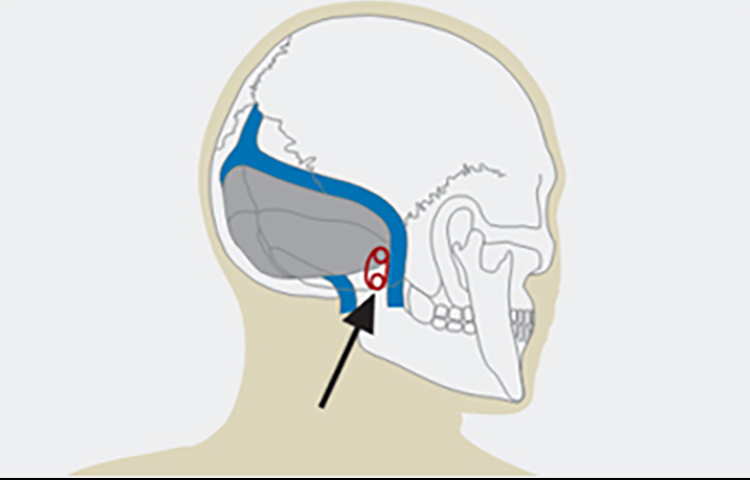

微血管减压术在面肌痉挛患者中的应用

微血管减压术在面肌痉挛患者中的应用

总结背景:面肌痉挛是一种运动性神经紊乱,表现为面部神经所支配的肌肉发生短暂的或持续的无意识收缩。发病率约为11/十万人。